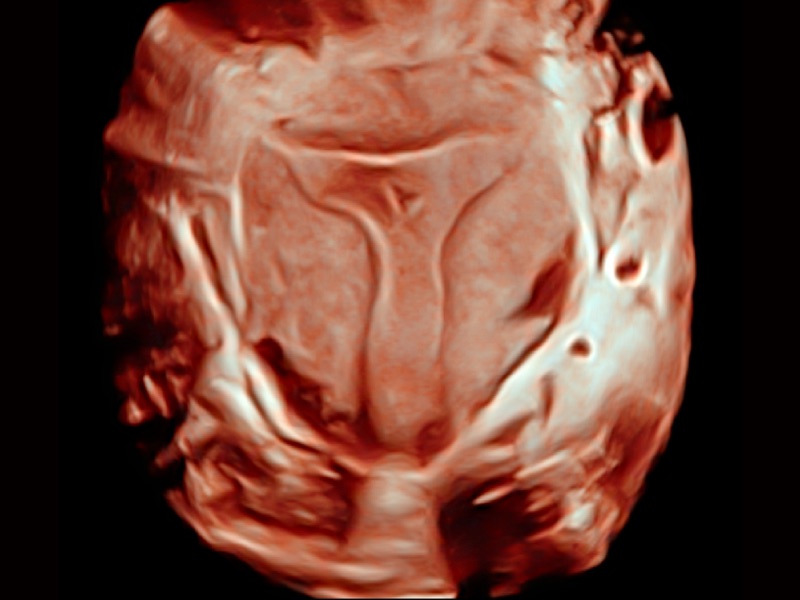

三维光影成像技术采用新型的渲染方式,增强边缘信息,使得轮显示清晰完整,为临床提供丰富、直观的三维结构,提供临床诊断准确性。

妇产科应用